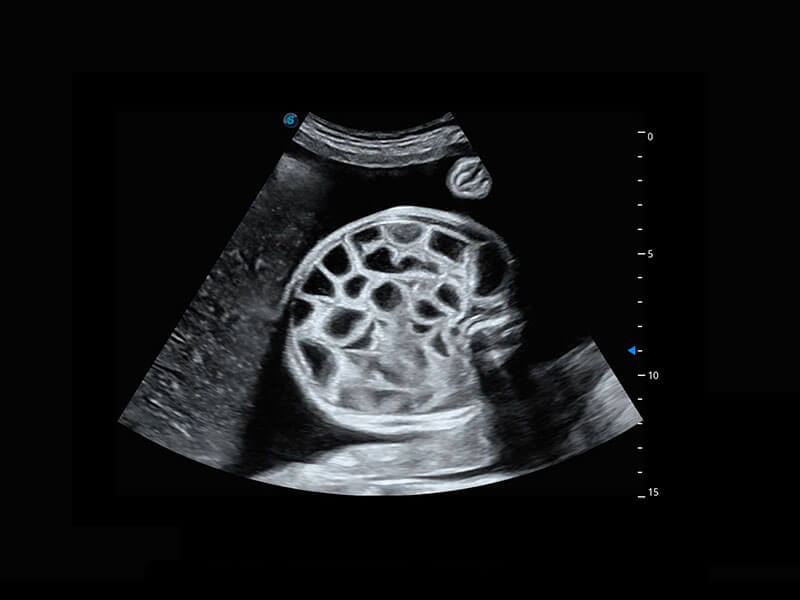

四腔切面

四腔心血流

右室双出口

胎心容积成像